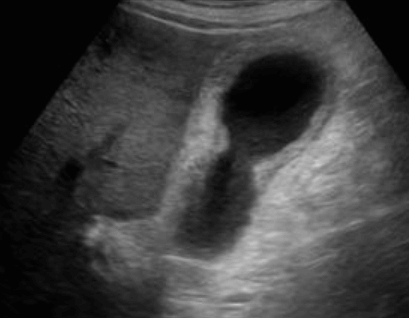

급성담낭염 US finding

- 담낭관내 결석

- 담낭벽이 두꺼워진다 ( GB wall thickness 3mm 이상)

- GB내강의 압력증가 및 확장 (width 5cm 이상)

- color doppler 시 GB wall 혈류증가 GB lumen bile sludge (내부에코증가)

- 급성담낭염은 담낭주위 액체저류 (pericholecystic fluid)

- 심한 RUQ pain (Murphy sign) : 젊은 환자에서는 대부분 Murphy sign이 있지만, 노인에서는 Murphy sign이 없더라도 급성 담낭염이 있는 경우가 많으므로 더 주의 깊게 관찰해야 한다.